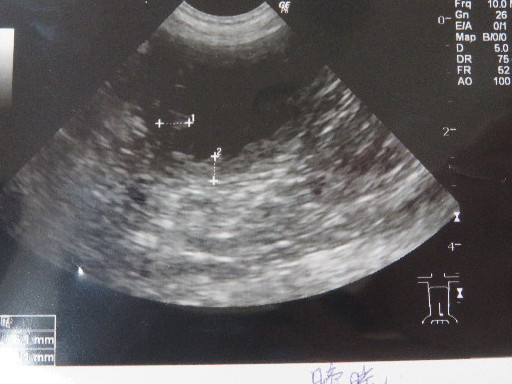

○今日で膀胱炎の抗生剤を18日間も連続で飲んでいるというのに、膀胱は今日も肥厚していました。

もしかしたらこの炎症が眼底出血と関係あるのかも??